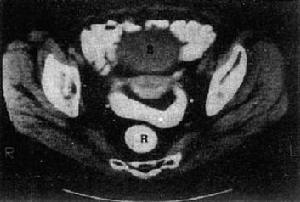

腹和盆腔聯合掃描腹和盆腔聯合掃描指掃描腹部和盆腔,進一步診斷腹部和盆腔病變。

1MRI診斷:MRI盆腔病變的一個重要方面就是確定病變的範圍,病變對周圍器官及不同組織層的侵犯程度。CT對於盆腔與腹膜後淋巴結病變的顯示具有較好的效果,MRI則可以更準確地判斷原發腫瘤局部擴散的範圍。與腹部超聲相比,MRI不受操作者技術的影響,同時對腹腔的準備亦無特殊要求。MRI掃描時間較長,檢查腸腔附近病變可使用平滑肌蠕動抑制藥物。膀胱區病變可囑患者飲水,保持膀胱充盈,使病變更易於顯示。磁共振成像診斷盆腔病變首先需要對盆腔器官以及其與周圍組織的解剖關係有詳盡的了解。同時需要熟悉各種組織的信號特徵才能做出正確的診斷。

3MRI切層方向及層厚:女性為盆腔MRI最常用的是橫斷面軸位和矢狀面T1WI、T2WI(必要時T2WIFS)。前者顯示盆腔臟器的前後左右毗鄰關係較好,後者顯示上下及前後關係較清晰;對子宮的檢查,以矢狀位T2WI最佳,清楚可顯示子宮固有解剖結構。如子宮畸形(雙角、平角子宮、子宮分隔、雙子宮必掃冠狀位T2WI,按子宮長軸掃描;男性如前列腺以橫斷位T2WI,可清楚顯示前列腺固有層解剖結構及冠狀位為好;對睪丸的檢查,以冠狀位T1WI、T2WI為佳;對膀胱癌的分期,則需作斜切面。其優點是各帶之間的分界亦趨於鮮明。如為較高磁場強度MR,則可選擇更小的層厚,薄層掃描有利於發現細小的結構及其病變